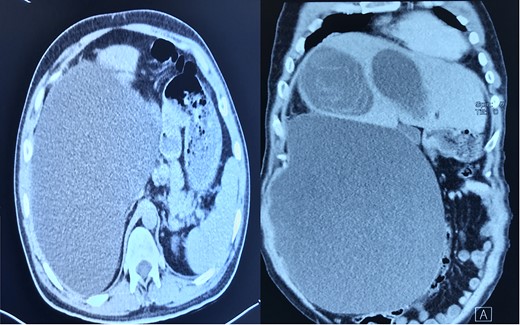

The biochemical tests were normal including the serum bilirubin level and liver enzymes. CT-scan of the abdomen showed two non-enhancing cystic lesions in the right lobe of the liver 11 cm and 10 cm containing undulating membrane (water-lily sign), and a third large cyst extending to the pelvic cavity 40 cm in length (features of multiple hydatid cyst of the liver), Fig. 2.

CT-scan of the abdomen showing three large cystic lesions related to the right lobe of the liver.